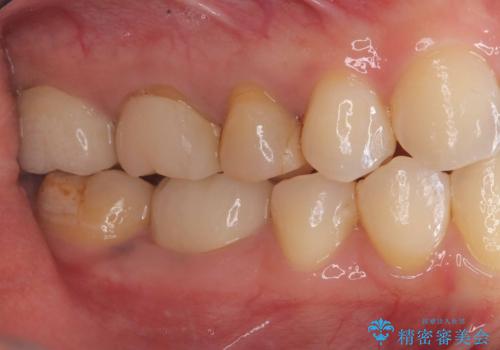

- 「銀歯を白くしたい」が主訴の患者様です。

銀歯を除去後、オールセラミッククラウンで治療を行いました。

被せ物のやり変えのみ希望だったため、根管とコアはさわっていません。

銀歯と虫歯を除去後、オールセラミッククラウンで治療を行いました。